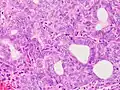

Serous carcinoma

Serous carcinoma is a Type II endometrial tumor that makes up 5–10% of diagnosed endometrial cancer and is common in postmenopausal women with atrophied endometrium and black women. Serous endometrial carcinoma is aggressive and often invades the myometrium and metastasizes within the peritoneum (seen as omental caking) or the lymphatic system. Histologically, it appears with many atypical nuclei, papillary structures, and, in contrast to endometrioid adenocarcinomas, rounded cells instead of columnar cells. Roughly 30% of endometrial serous carcinomas also have psammoma bodies.[20][46] Serous carcinomas spread differently than most other endometrial cancers; they can spread outside the uterus without invading the myometrium.[20]

The genetic mutations seen in serous carcinoma are chromosomal instability and mutations in TP53, an important tumor suppressor gene.[48]